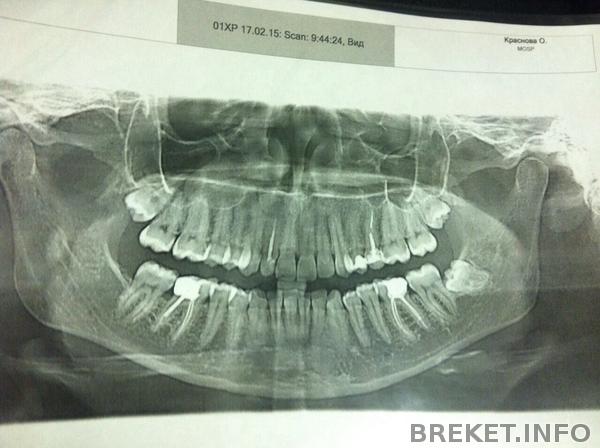

Вообщем, спустя год я вернулась к вопросу установки, вплотную и серьезно, удалось скопить часть денег, чтобы приступить к выполнению моей давней мечты. Выбрала место, врача. Пришла на консультацию и естественно направили первым делом на снимок, смотреть есть ли у меня зубы мудрости в зачатках. Оказалось у меня их целых 3....ортодонт говорит нужно удалить все, а потом ставить систему. Боюсь удалять до жути

у меня 2 вверху и 1 внизу. Скажите, обязательно сразу 3 до установки удалять или можно внизу например, через какое то время после установки брекетов удалить? Просто боюсь уже после удаления первого забью на все и брошу ![]()

А вот, собственно, и я в рентгене)))))

А где у вас на НЧ зуб мудрости с левой стороны?Его там от природы не было?

Логарифм Брекета, его и не было)) от природы))) рада была бы если б и остальных не было, ну или один хотя бы)))